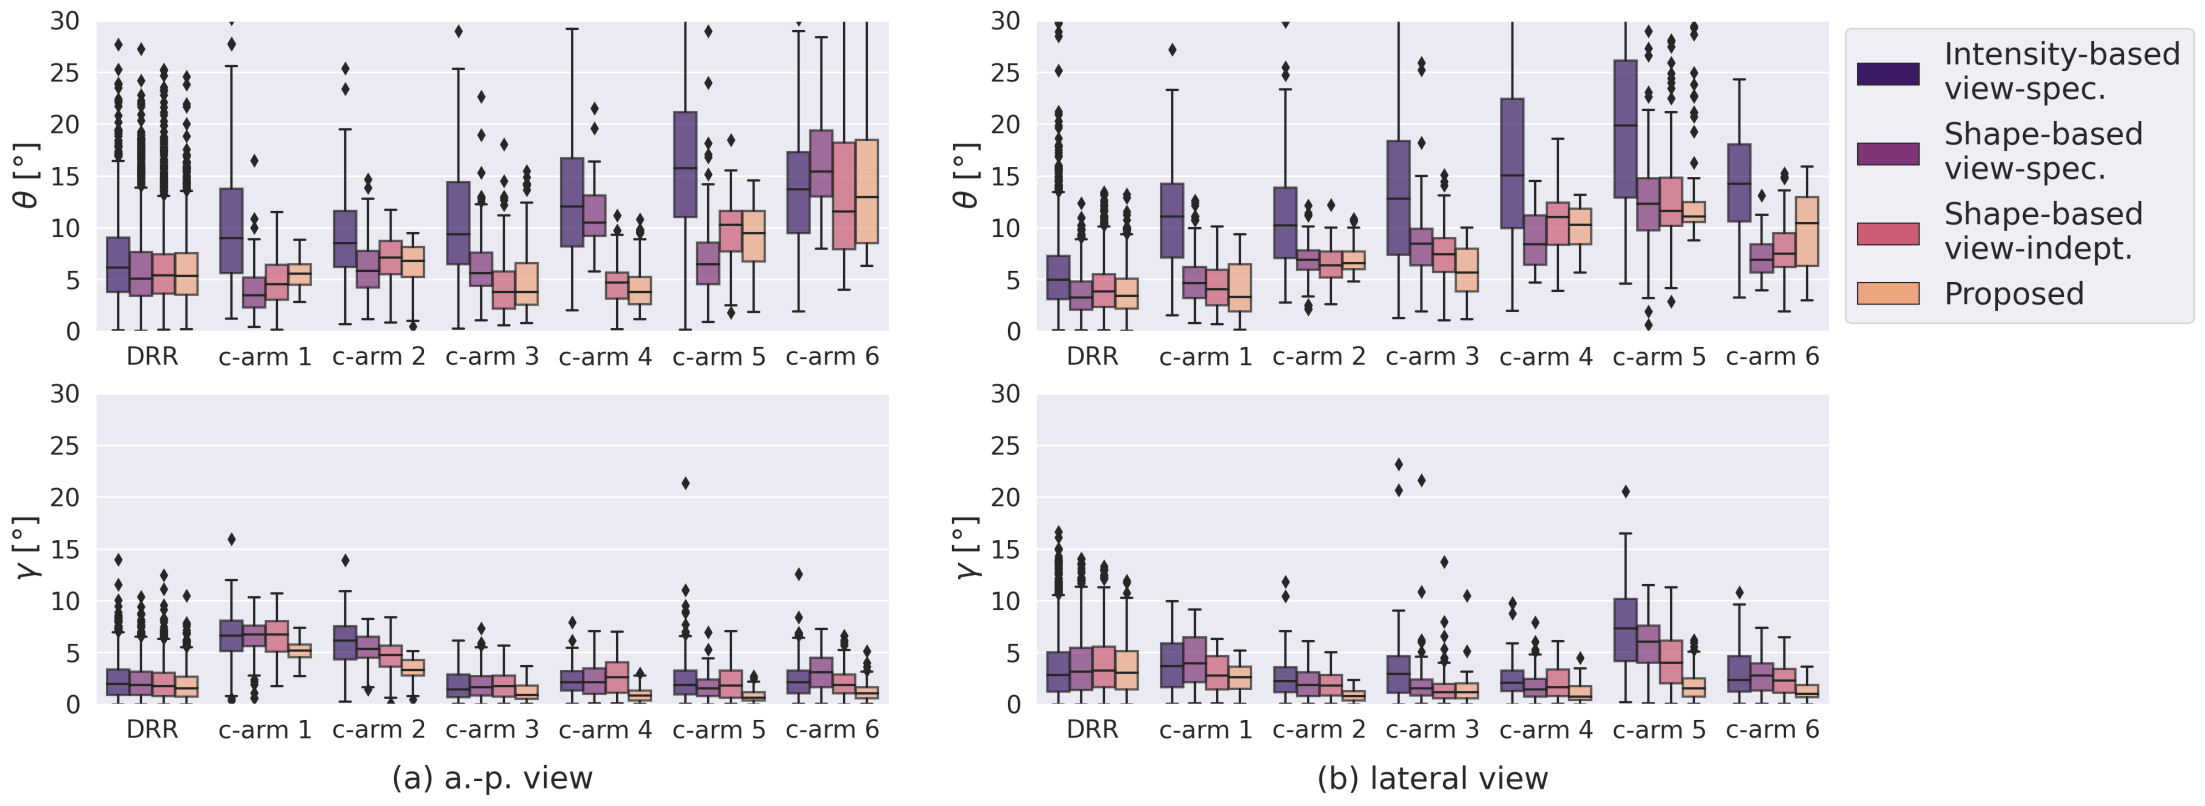

Positioning performance was evaluated based on the angle between the principal rays of the ground truth and predicted pose and the mean absolute error () of in-plane rotation . The interrater variation of the reference standard planes defined by two independent raters serves as an upper bound for the reachable accuracy of a C-arm positioning approach trained on the reference annotations. It was assessed in terms of orientation differences (, ).

In an ablation study, the proposed shape-based view-independent pose regression was compared to view-specific direct intensity-based pose regression [11]. Further, the complete pipeline (2-step) is compared to a 1-step segmentation-based approach trained view-specific and view-independent (Fig. 4). Evaluation was performed on the simulated test DRRs and cadaveric X-rays (Fig. 5).

View-independent vs. view-specific networks: While the view-specific networks perform significantly better (lateral) or comparable (a.-p.) on the simulated data, the view-independent networks perform significantly better (a.-p.) or comparable (lateral) on the real data.

1-step vs. 2-step: The proposed 2-step approach performs significantly better or comparable than a 1-step shape-based pose regression approach on most validation cases (8/12) in viewing direction . Regarding the rotation, the 2-step approach improves performance across all validation cases.

Generalization from DRR to X-ray: The shape-based pose regression network combined with joint view-independent training clearly boosts the performance compared to direct intensity-based pose regression from to .